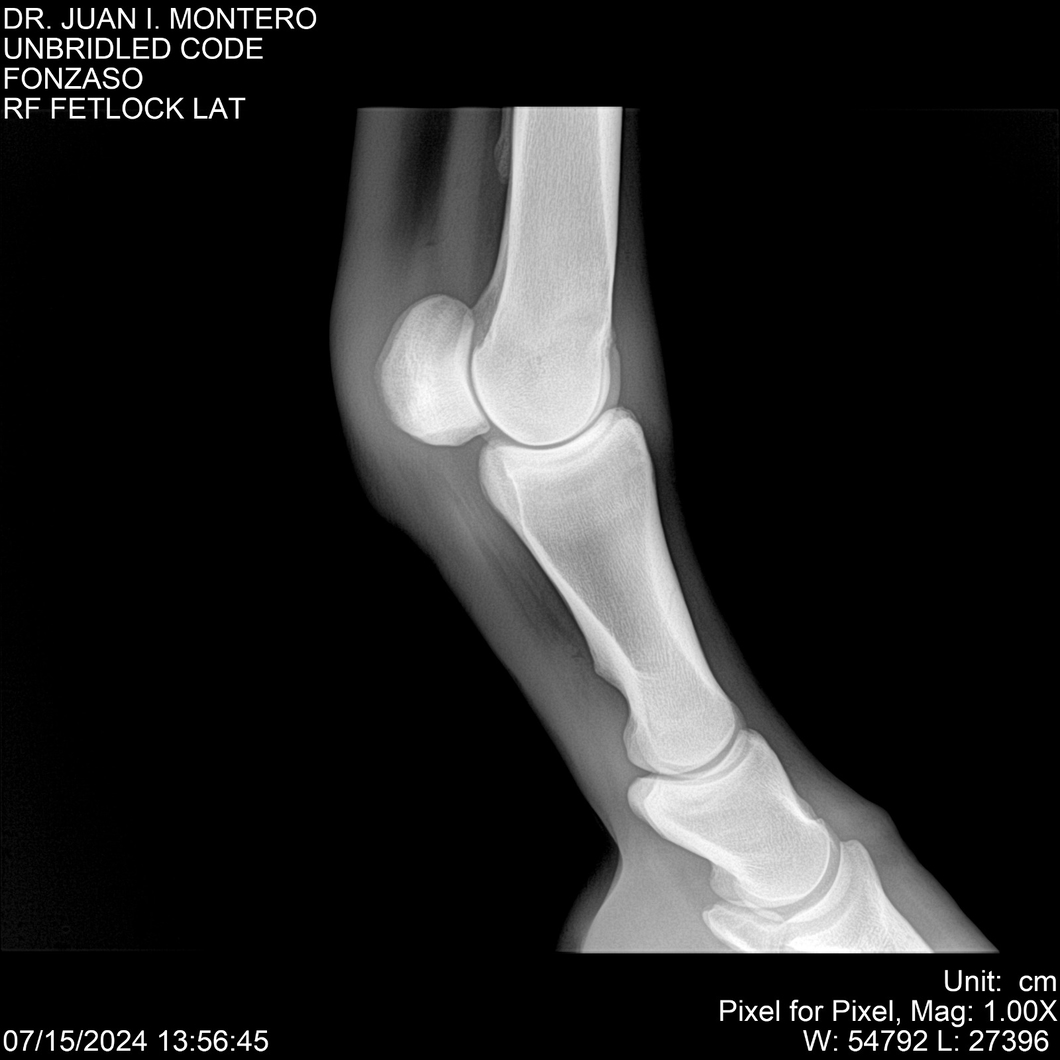

• Empresa: Abelenda N. R., Walter Hugo